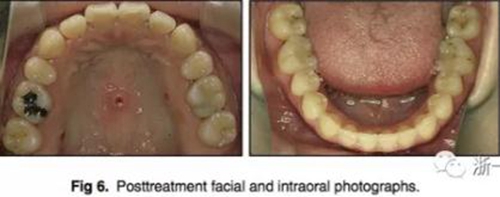

五、治療結(jié)果

治療后數(shù)據(jù)提示治療目標(biāo)達(dá)成。面相結(jié)果提示微笑及側(cè)貌得到改善(圖6)。達(dá)到了安氏I類(lèi)尖牙關(guān)系和安氏II類(lèi)磨牙關(guān)系,形成尖牙保護(hù)合。牙齒中線無(wú)偏斜,達(dá)到理想的覆合覆蓋,Spee曲線得到整平。